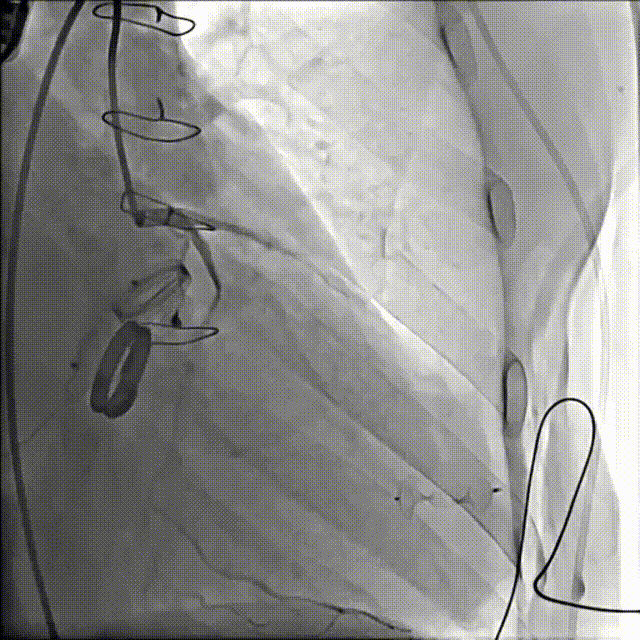

手术操作

1.患者平卧位,食道超声检查瓣周漏位置及大小,并引导穿刺心尖,选择7F鞘管通过10点位置瓣周漏口,将单弯导管送入左心室,置换超硬导丝至左心室,选择12-14mmPDAO封堵10点位漏口。